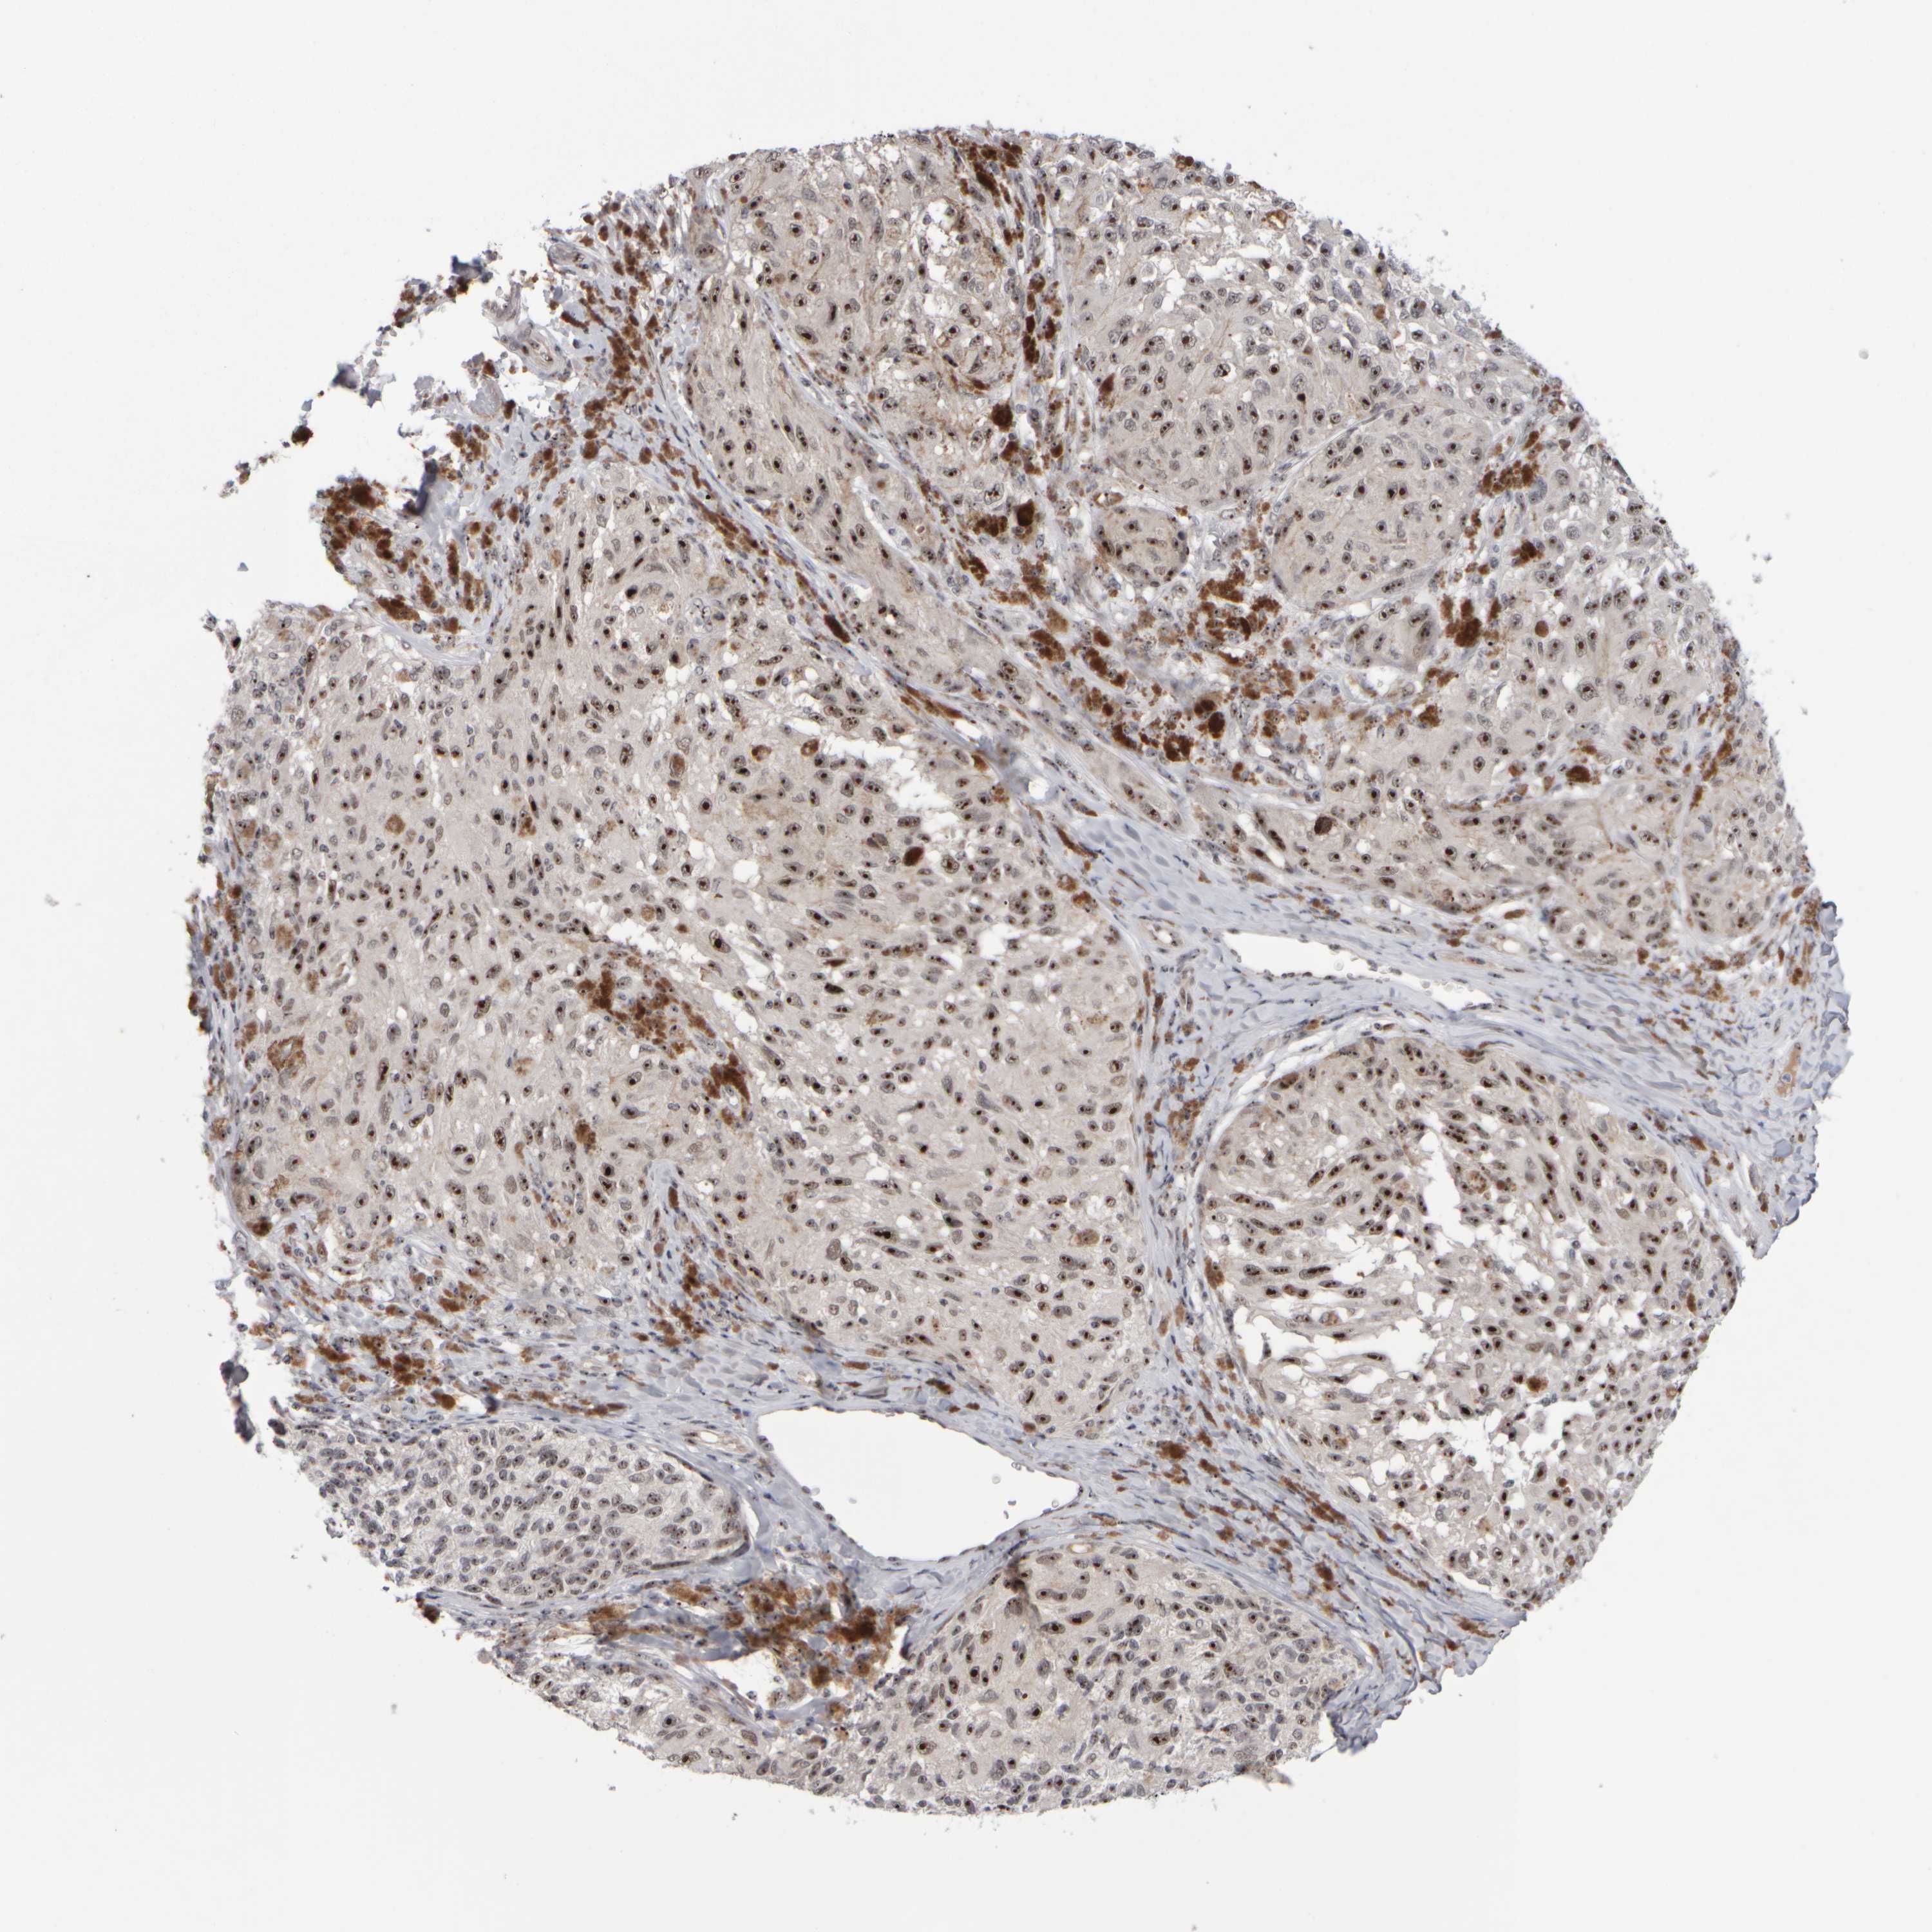

MELANOMA - Protein expressioni

A mouse-over function shows sample information and annotation data. Click on an image to view it in a full screen mode. Samples can be filtered based on level of antibody staining by selecting one or several of the following categories: high, medium, low and not detected. The assay and annotation is described here.

Note that samples used for immunohistochemistry by the Human Protein Atlas do not correspond to samples in the TCGA dataset.

Antibody stainingi

Antibody staining in the annotated cell types in the current human tissue is reported as not detected, low, medium, or high, based on conventional immunohistochemistry profiling in selected tissues. This score is based on the combination of the staining intensity and fraction of stained cells.

Each image is clickable and will lead to virtual microscopy that enables deeper exploration of all samples and also displays staining intensity scores, fraction scores and subcellular localization as well as patient and tissue information for each sample.

Antibody HPA023608

Staining

High

Medium

Low

Not detected

Intensity

Strong

Moderate

Weak

Negative

Quantity

>75%

75%-25%

<25%

None

Location

Nuclear

Cytoplasmic/membranous

Cytoplasmic/membranous,nuclear

Malignant melanoma, NOS

Malignant melanoma, Metastatic site